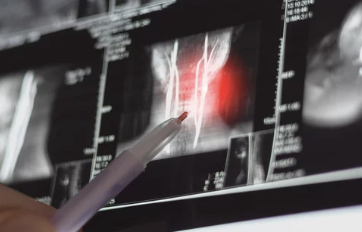

목디스크의 정의

목디스크(경추 추간판 탈출증)는 목뼈 사이에 있는 디스크(추간판)가 탈출하거나 찢어져 신경을 압박하는 상태를 말합니다. 이로 인해 통증, 저림, 움직임 제한 등이 발생합니다.